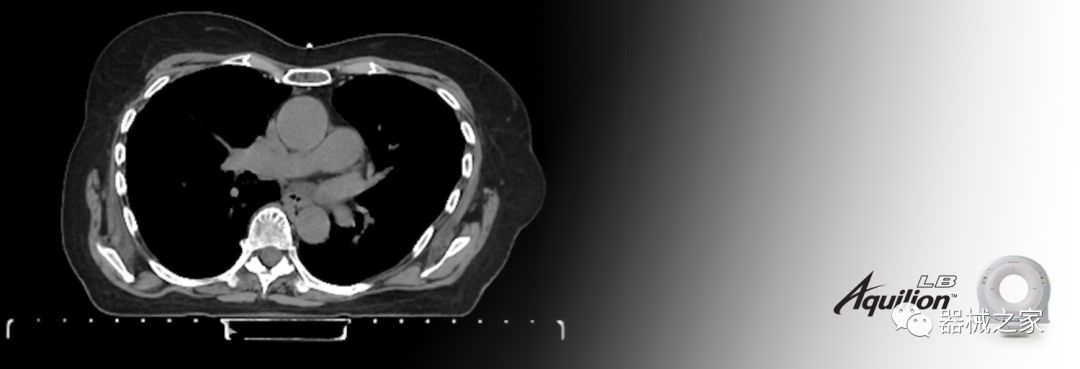

在以患者為中心的放射腫瘤學(xué)領(lǐng)域,計(jì)算機(jī)斷層掃描(CT)的可訪問性,可重復(fù)性和靈活性至關(guān)重要。為了建立這些價值,佳能醫(yī)療系統(tǒng)美國公司現(xiàn)在正在擴(kuò)大其放射腫瘤學(xué)CT模擬產(chǎn)品,包括Aquilion Prime SP和Aquilion Lightning 80高級CT系統(tǒng)。除了Aquilion LB之外,Aquilion Prime SP和Aquilion Lightning 80現(xiàn)在還包括放射治療(RT)選項(xiàng),可為腫瘤學(xué)規(guī)劃提供高質(zhì)量的CT成像和精密工具。

RT套件可在新系統(tǒng)或現(xiàn)有系統(tǒng)上使用,提供經(jīng)濟(jì)高效的解決方案,可提高CT掃描儀的使用率,效率和工作流程,包括:

擴(kuò)展視野(EFOV)可以看到更多的解剖結(jié)構(gòu)。Aquilion LB采用85 cm EFOV,而Aquilion Prime SP和Aquilion Lightning 70采用70 cm EFOV。

RT平臺桌面掃描在同一位置,舒適輕松。

呼吸門控為呼吸運(yùn)動管理提供強(qiáng)大的靈活性; 和LAP激光器可改善室內(nèi)患者設(shè)置和技術(shù)人員工作流程。

佳能醫(yī)療的Aquilion Lightning 80掃描儀還以緊湊,經(jīng)濟(jì)的包裝提供高質(zhì)量的成像。Aquilion Lightning 80旨在可靠,高效地運(yùn)行,在繁忙的環(huán)境中生成高質(zhì)量的圖像。

兩個CT系統(tǒng)均采用0.5 mm x 80排PUREViSION探測器技術(shù)(可配置并從80-160現(xiàn)場升級),78 cm孔徑,50 cm視野,AIDR(自適應(yīng)迭代劑量減少)3-D和SEMAR(單個)能量金屬神器減少)技術(shù)。

Aquilion LB專為滿足腫瘤學(xué)挑戰(zhàn)而設(shè)計(jì),同時優(yōu)先考慮患者護(hù)理。Aquilion LB的內(nèi)徑為90 cm,能夠幫助復(fù)雜的患者設(shè)置并提高患者的舒適度。CT模擬定位可以輕松鏡像放射治療定位,更加自信。該系統(tǒng)采用0.5 mm x 16排(32層)PUREViSION探測器技術(shù),70 cm視野,AIDR 3D和SEMAR技術(shù)。